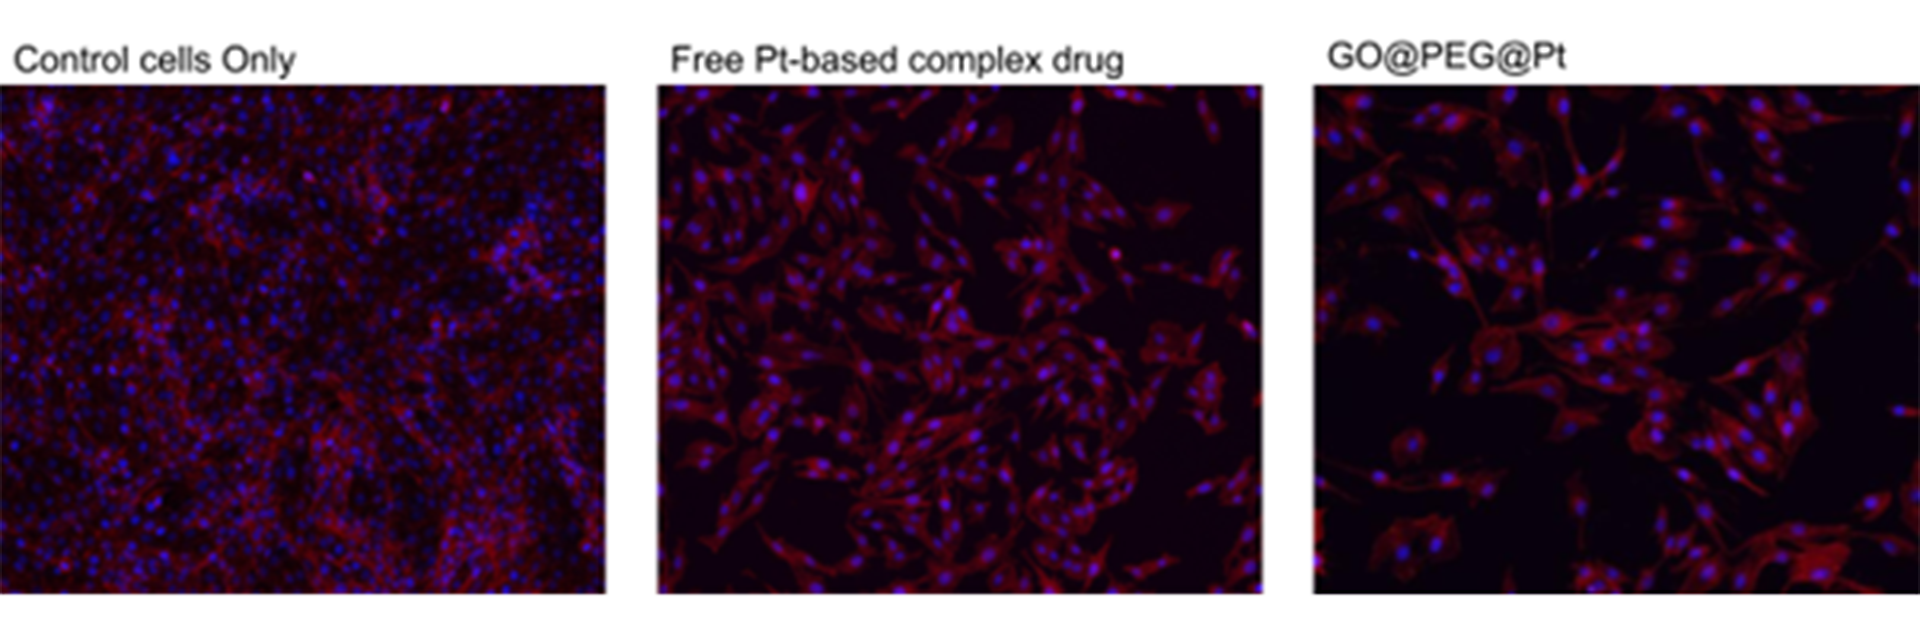

The platinum-based complexes were afterwards anchored covalently on the surface of the platform. Our recent publication (Zarska et al., Nanomaterials, 2022) showed a synergy effect between the nanoplatform and the bound drugs, increasing the therapeutic effect, as demonstrated in Fig. 2. The nanoplatform accomplishes excellent cellular proliferation inhibition in osteosarcoma, strictly related to increased cellular uptake. To a lesser extent, this cellular internalisation was seen in glioblastoma.

It was also shown that the proposed GO@PEG nanoplatform is promising for inhibiting cell migration and minimising the metastatic process. Thus, the GO@PEG nanoplatform stands as an exciting tool in cancer treatment, with the possibility of targeting diverse types of cancers.